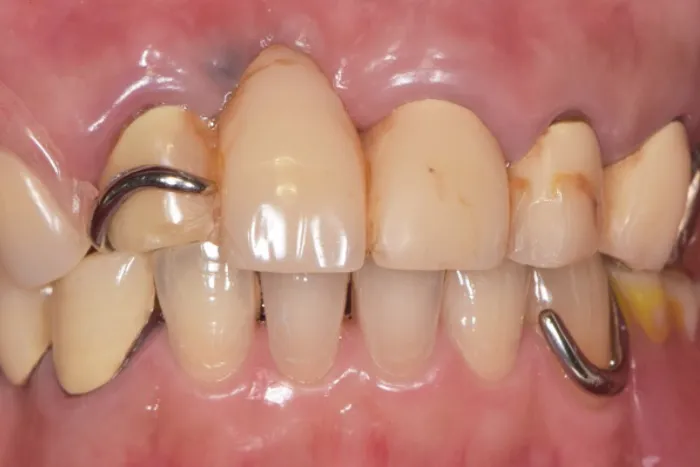

症例② 前歯が一本だけ長いのが気になる

Before

After

| 主訴 | 前歯が一本だけ長いのが気になる |

|---|---|

| 治療期間 | 8ヶ月 |

| 治療費 | 結合組織移植術 77,000円 ※保健治療の金額は含みません |

| 治療内容 | 根管治療・結合組織移植術・レジン前装冠 |

| 治療のリスク | 術後の腫脹・出血 / 歯肉退縮による金属色の露出 |

▲治療のコメント

歯を抜いて歯茎が退縮してしまったことが原因で歯が長くなっていました。なので、上顎口蓋から結合組織を移植することで退縮した歯肉を再建しました。その上でブリッジのやり直しを行いました。